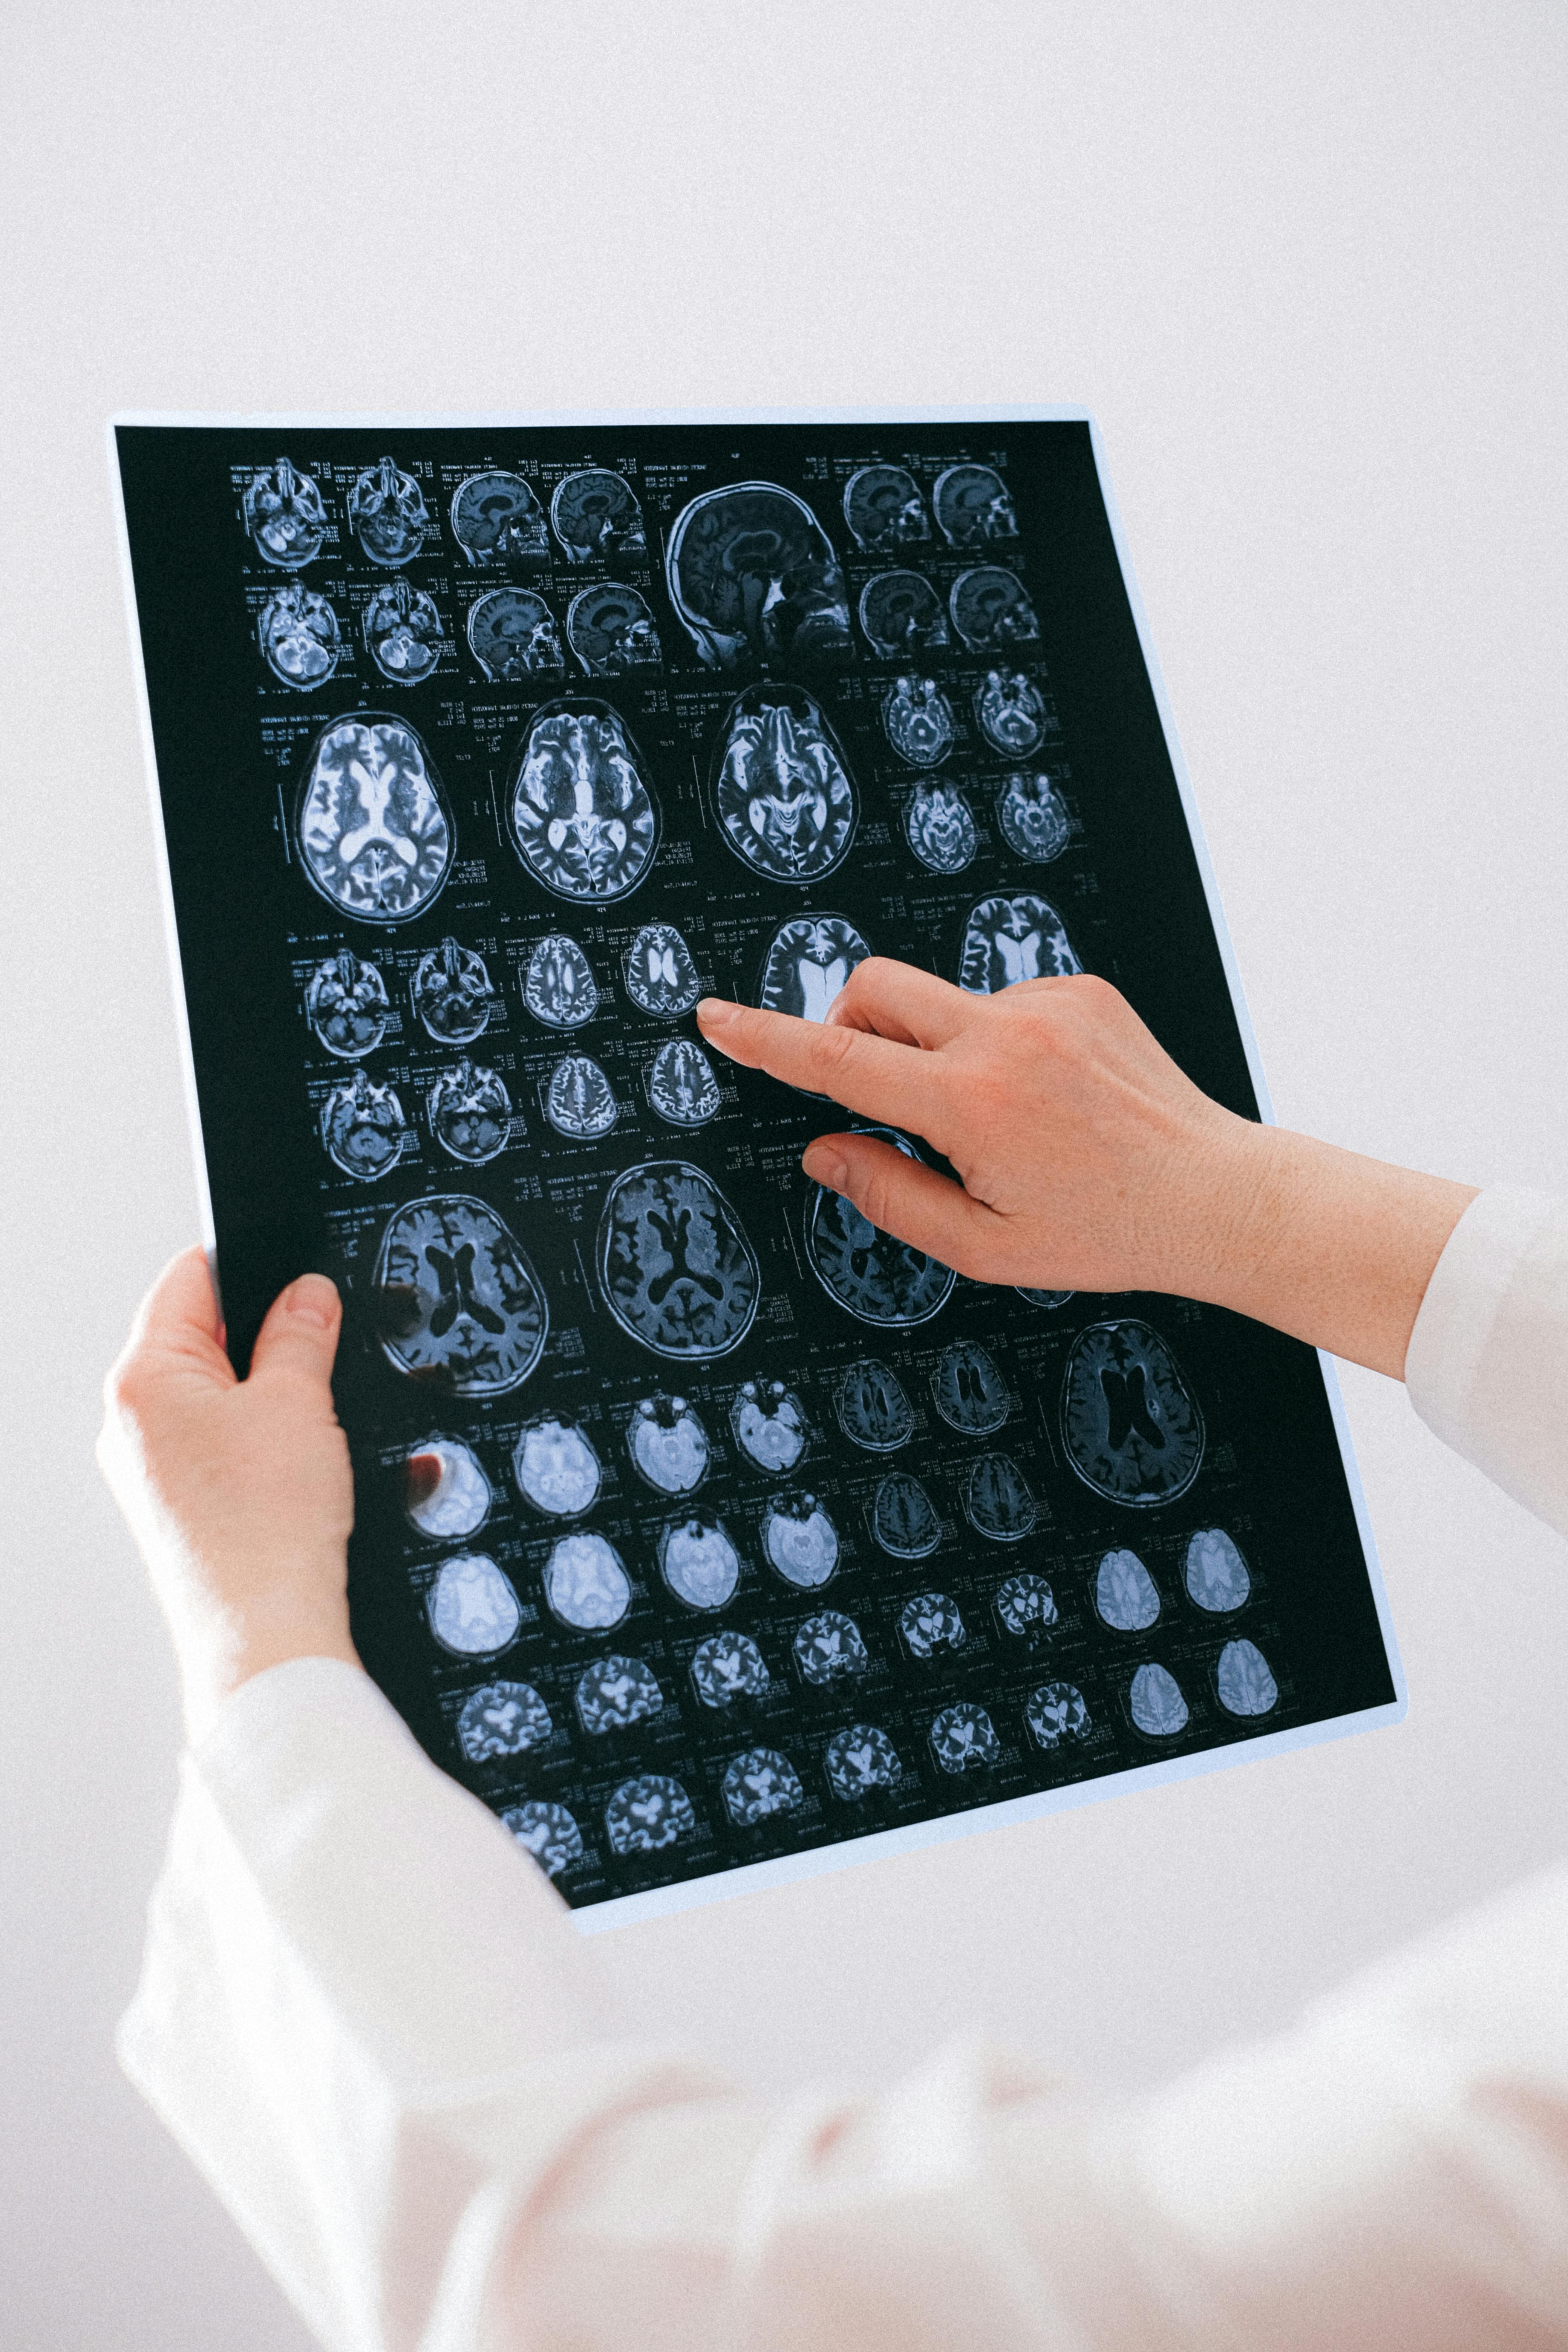

치매는 기억력, 사고력, 언어 능력 등 인지 기능이 저하되는 증상을 포괄적으로 지칭하는 용어예요. 반면, 알츠하이머병은 치매의 한 종류로, 가장 흔한 형태의 퇴행성 뇌질환이에요. 알츠하이머병은 전체 치매 환자의 50~70%를 차지하고 있어요.

치매는 여러 가지 원인에 의해 발생할 수 있어요. 대표적인 종류로는 알츠하이머병, 혈관성 치매, 루이체 치매, 전측두엽 변성 등이 있어요. 각 종류마다 증상과 진행 속도가 다르기 때문에, 정확한 진단이 중요해요.

알츠하이머병은 여러 단계로 나뉘어져 있어요. 초기에는 최근 기억의 감소가 나타나고, 점차 언어 사용의 어려움, 일상 생활의 어려움으로 발전해요. 마지막 단계에서는 심각한 인지 장애와 행동 문제까지 발생할 수 있어요.